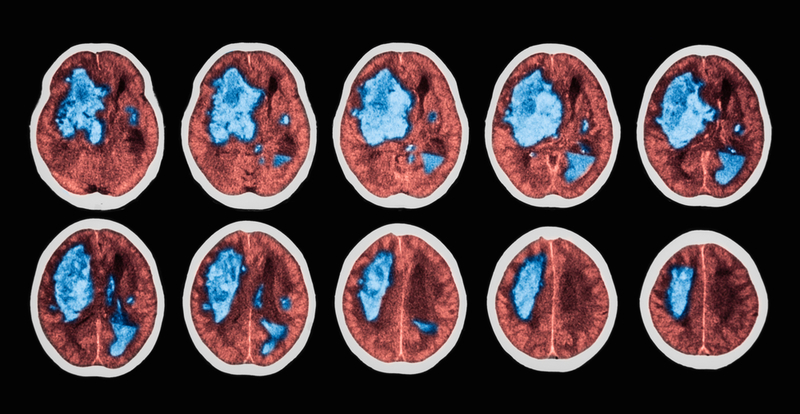

Haemorrhagic stroke highest in northeastern states: Lancet study

One in three people, between 30-69 years, living in India's northeastern states, suffered premature deaths due to haemorrhagic stroke in 2015, and were about three times higher than the national average, alarming research, led by one of an Indian-origin, has found.

Hypertension is the primary risk factor for haemorrhagic stroke and consumption of excessive salt could be one of the reasons. According to the study, high blood pressure, inadequate stroke care and novel risk factors such as endemic infections might have played a role in increased mortality rates in these regions, representing a sixth of the country's population.